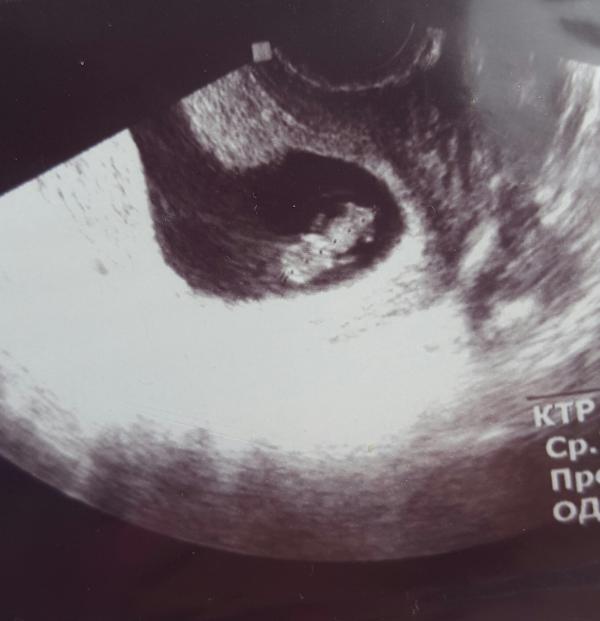

Поделюсь с вами самыи мимимишным снимком, и это всего 9 неделя)) когда увидела какой там пупсик, улыбка не сходила с лица. эхх, времечко)) ни пуза, ни токсикоза, ни бессонных ночей. А сейчас уже на низком старте)